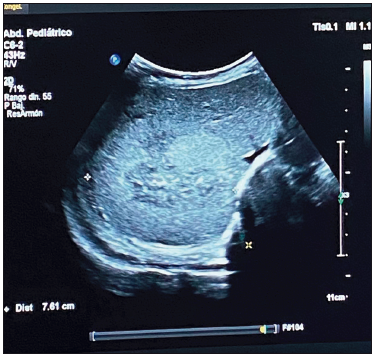

Al ingreso presentó hipotonía axial sin dismorfias. Se solicitó una ecografía abdominal en la que se visualizó una imagen ecogénica hepática (segmento VI - VII), con bordes difusos, de 4 x 3.5 x 3.1 cm, que coincidió bioquímicamente con el aumento de las enzimas hepáticas y leve anemia. La AFP estaba dentro de valores normales para la edad (42,334 ng/ml), con plaquetas normales. (Figuras 1 A B C).

Figura 1. A